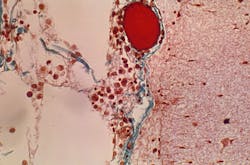

Elevated levels of plasminogen and plasmin have been found to be a common factor in people with diabetes and preexisting heart, lung and kidney conditions. Plasminogen is an inactive substance in the blood. When substances in the cells of the blood vessels activate plasminogen, it generates plasmin, an enzyme that removes blood clots from the blood. Higher-than-normal levels of both of these chemicals can lead to severe bleeding.